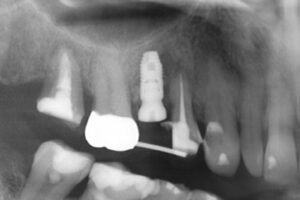

骨のない部分を骨造成し、インプラントを入れた症例

著しく骨が吸収されていたため、そのままインプラントを入れることはできない

人工骨を使った骨造成術を行い骨が再生するのを半年程待ち、インプラントを入れた

骨造成術、インプラント手術ともに術後の痛みや腫れもなく順調に経過し、治療後のレントゲン画像でも十分な骨の再生が認められる。